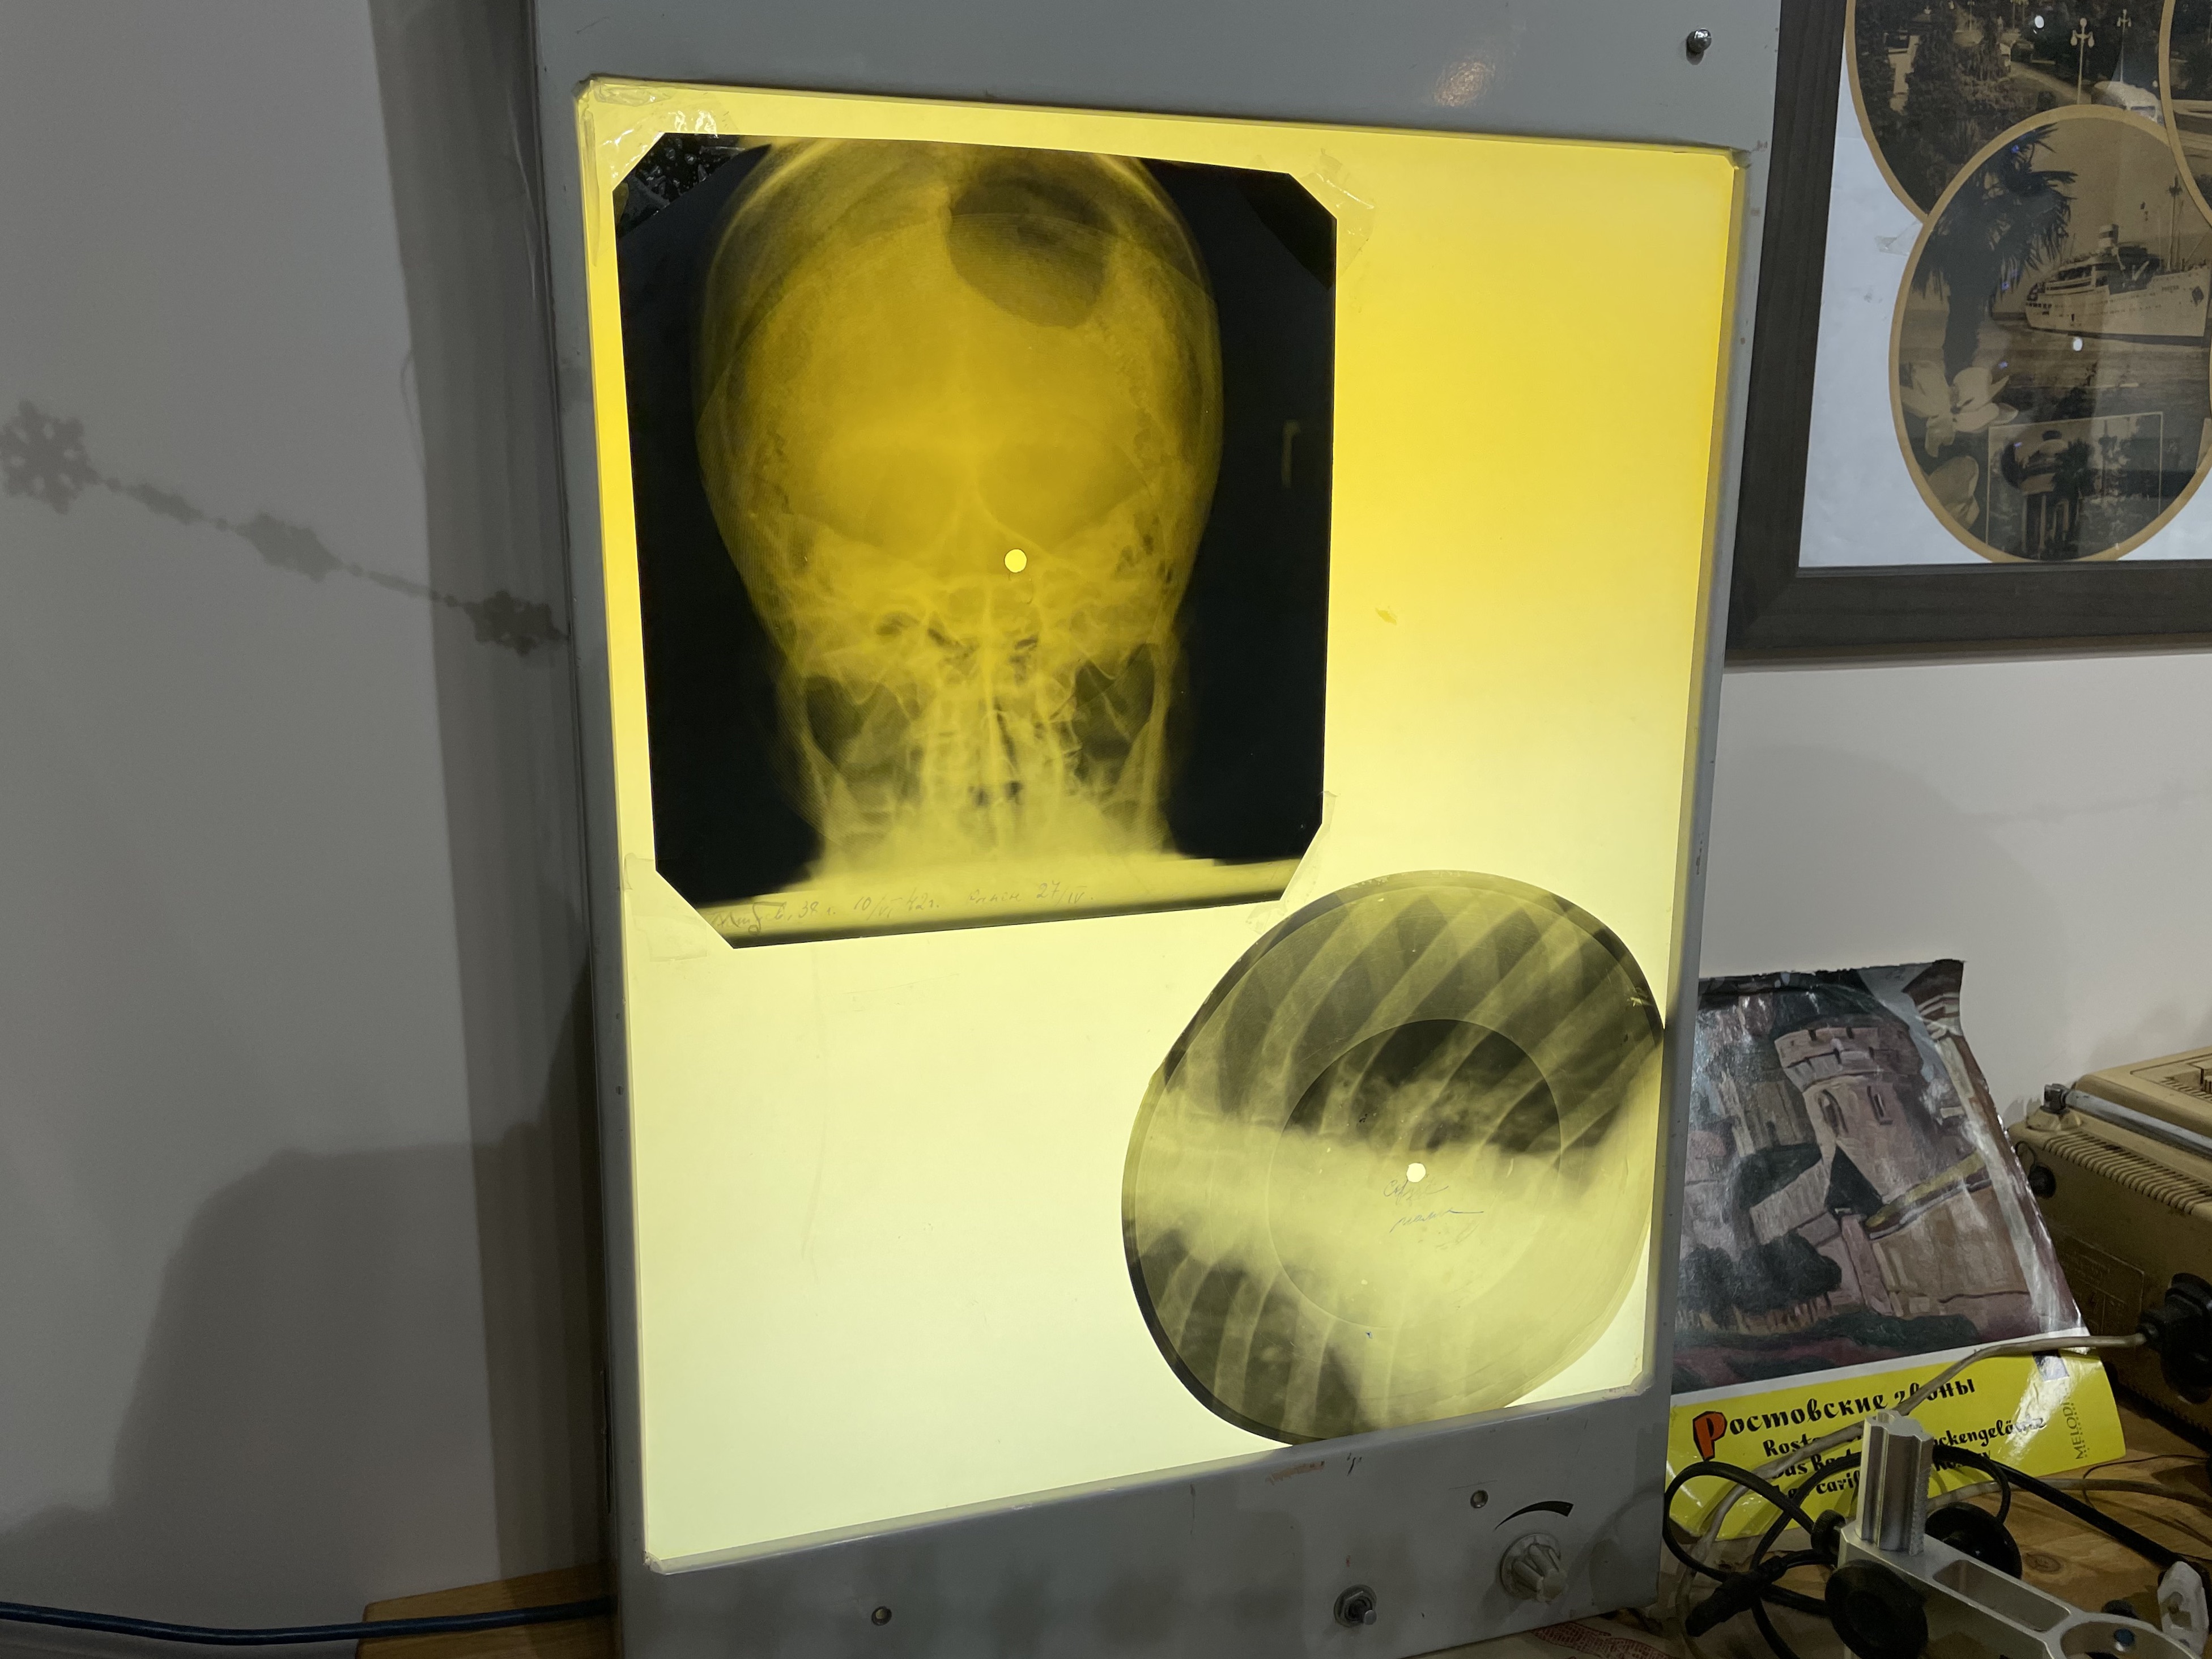

Рентгеновские технологии: усиленные экраны 35x35

Раздел: Фотопутеводитель